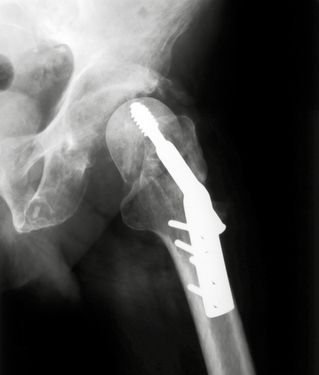

hip-implant-xrayHip implants aren’t meant to last forever. However, they are expected to function well for several years after implantation, then be replaced.

Some implants, however, fail within just a few years of being implanted, possibly due to defective design. A badly designed implant may be unstable if it does not seat properly on the bone.

In some cases, the failed implant needs to be surgically replaced using a procedure known as revision surgery. While hip replacement revision surgery is similar to primary hip replacement surgery, it’s more complicated and takes more time. With those differences comes a greater risk of complications.

The details of revision surgery vary on a case-by-case basis, but generally it consists of removing the failed implant and replacing it with a new one. Depending on the nature of the failure, the surgeon may remove only part of the implant or may instead remove the entire mechanism.

Then the remaining bone must be prepared to receive the new implant, either by cutting away more bone or by affixing a bone graft where more bone is needed. Finally, the new hip implant is put in place.